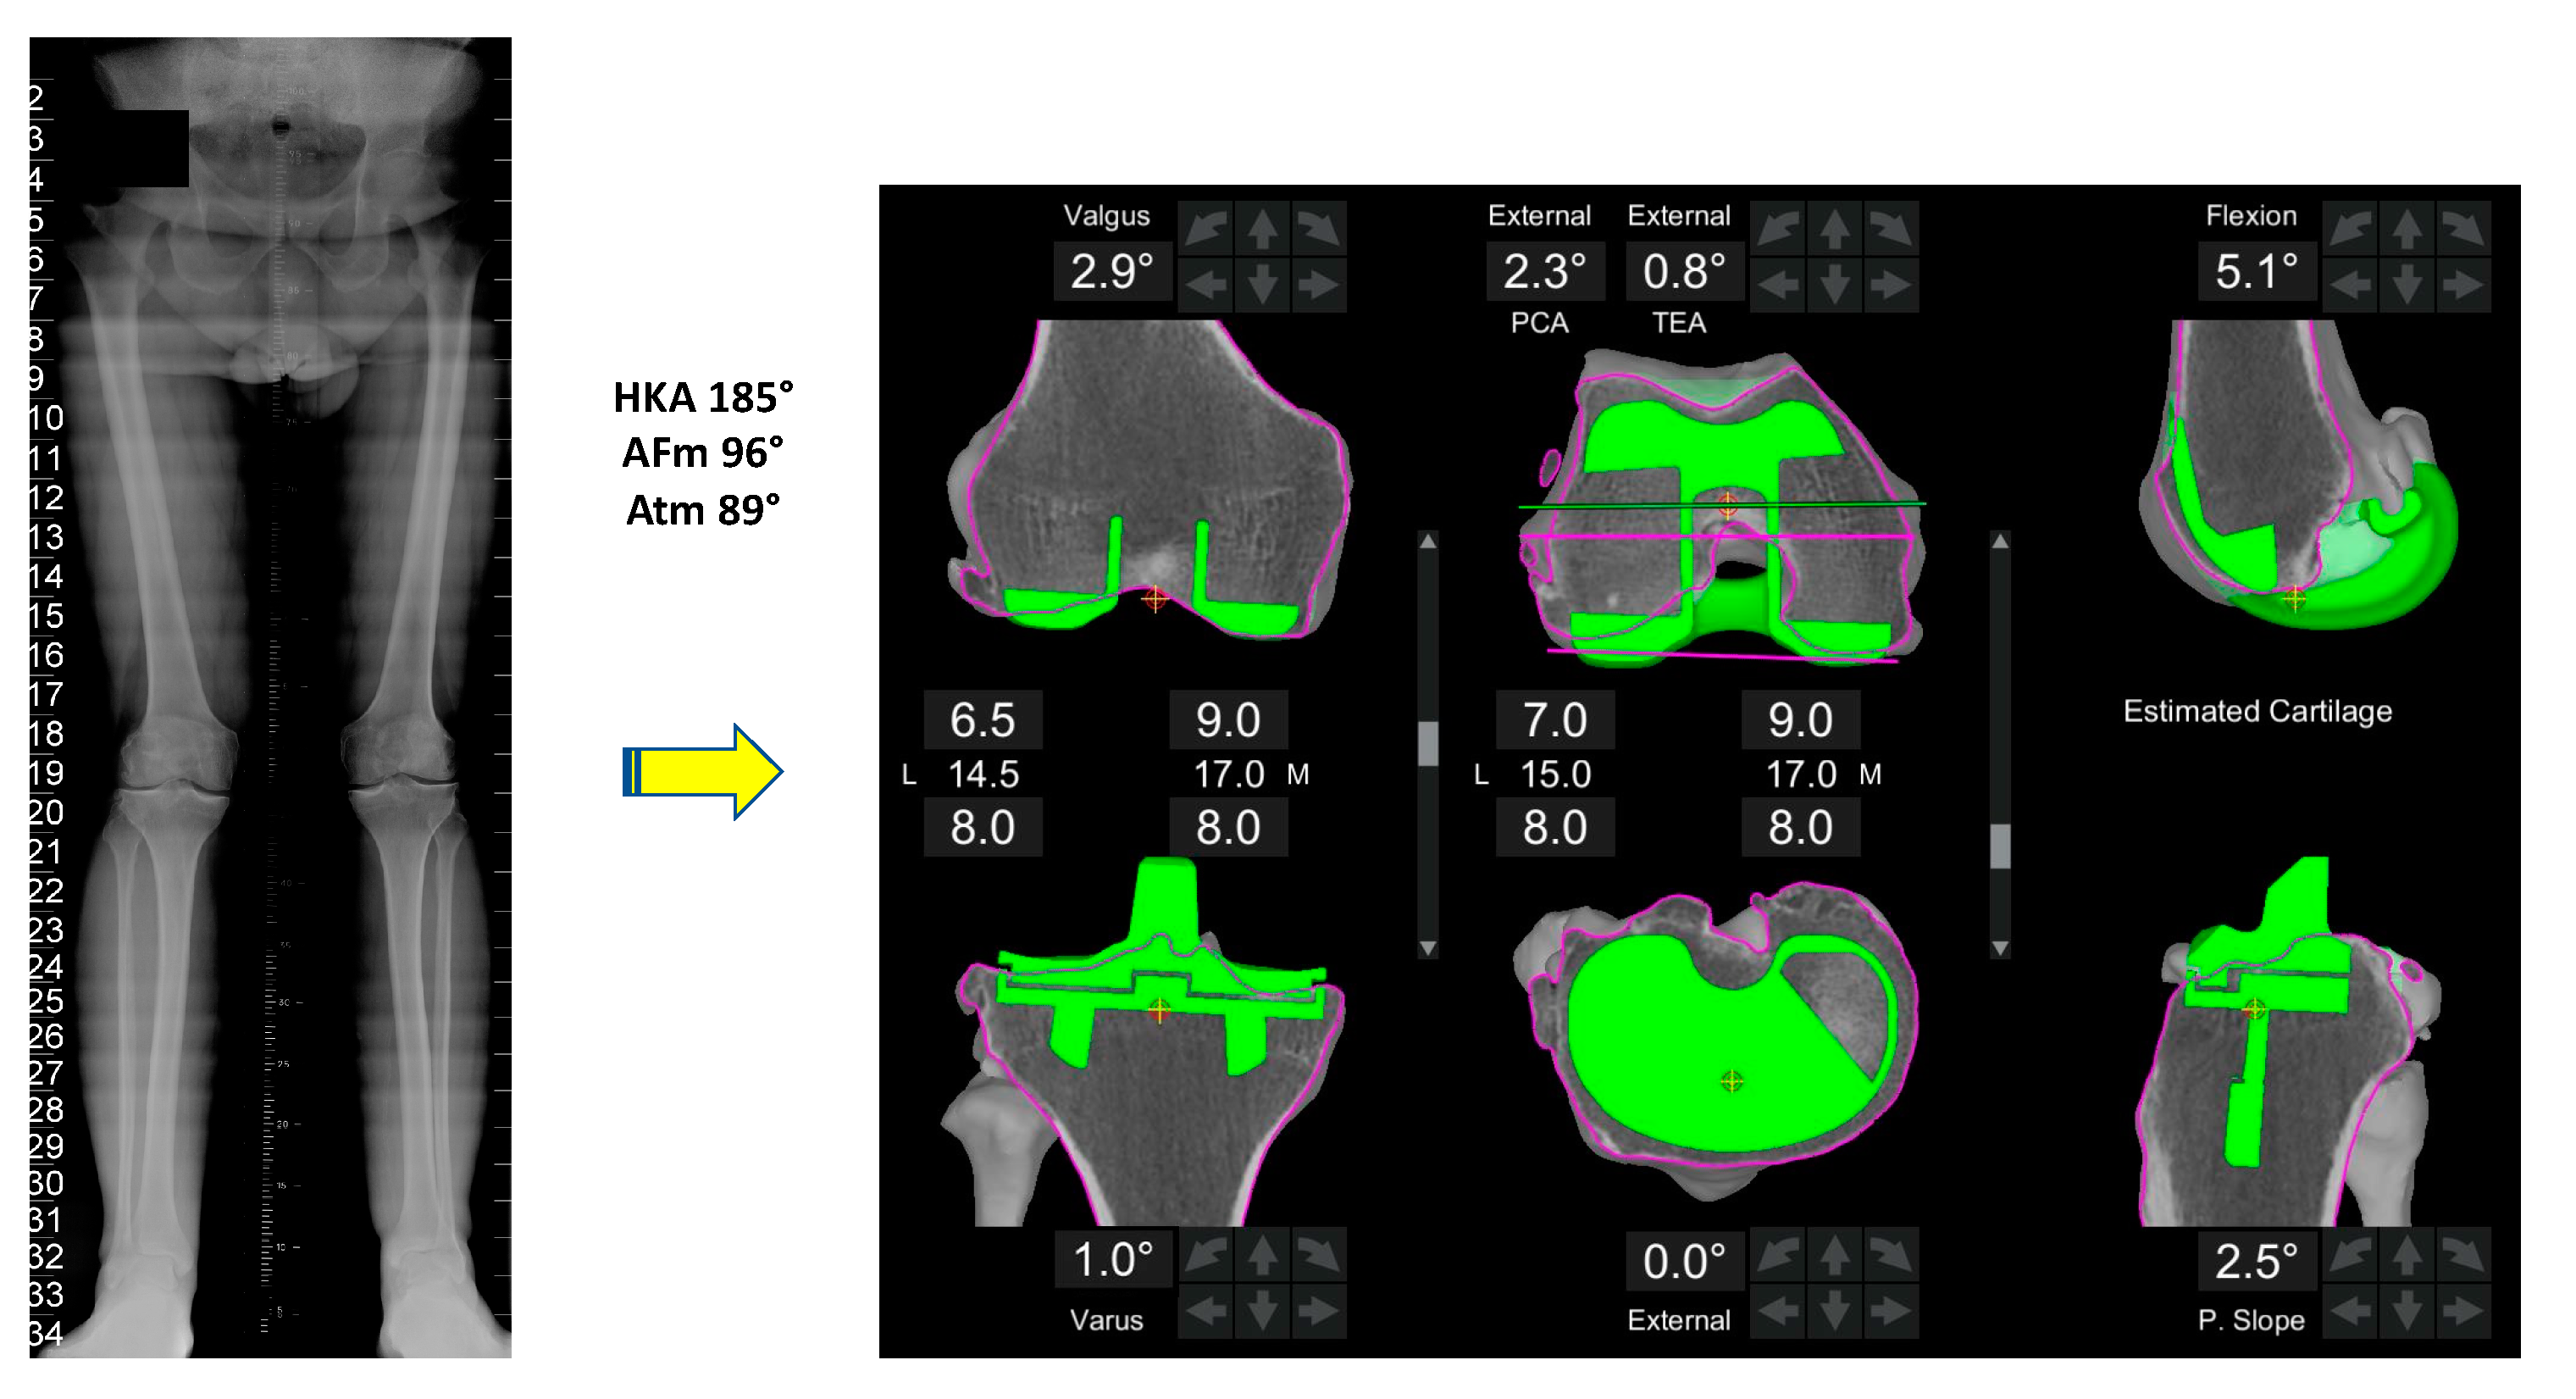

- Coronal plane: femoral implant positioning is planned according to the LDFA with an upper limit of 6° mechanical valgus in femur. To achieve a final alignment with a maximum valgus of 183°, varus positioning on the tibia may be required unless there is extra-articular varus deformity in either the femur or tibia.

- Resection depth: For distal femoral resection, the medial femoral condyle represents the reference point. A smaller amount of bone is typically removed from the lateral femoral condyle because of wear and morphological variation that is encountered here. It is 9 mm resection if planned from the medial distal femoral condyle and typically 4-6mm from the lateral femoral condyle. The target of 9 mm resection is based on 7 mm of bone plus 2 mm of cartilage.

- Size: The tibia is initially sized with rotation to 0° on the axial view of the CT scan with the aim of having maximal cortical contact with no implant overhang.

- Coronal plane: tibial implant position is aligned to provide the closest match to the medial proximal tibial axis (MPTA) and balance flexion and extension gaps in a range from 2° of valgus to 6° of varus. In the valgus morphotype, in order to avoid a residual valgus HKA > 3° valgus, the tibia is often cut orthogonal to its mechanical axis. A valgus tibial position more than 2° should be avoided. Valgus tibial positioning is reserved for cases where the deformity is an extra-articular tibial deformity, which in our experience is uncommon.

- Sagittal plane: tibial implant position is set to match the patient’s native posterior tibial slope with a limit of 3° when using a PS implant and can be modified to balance the flexion gap if necessary. A limit of 10° combined femoral-tibial flexion is allowed.

- Tibial resection: 8 mm resection is planned from the medial tibial plateau (6 mm bone + 2 mm cartilage) based on subchondral bone and an average cartilage depth of 2 mm in the normal knee, to use a 9 mm polyethylene insert. Resection from lateral tibial plateau is, typically less i.e., 4–6mm due to wear, but also to account for the extra articular tibial valgus deformity that often co-exists in the valgus morphotype [31]. This gives a combined planned resection of 17 mm medially, which is the combined thickness of this implant with its thinnest tibial liner.